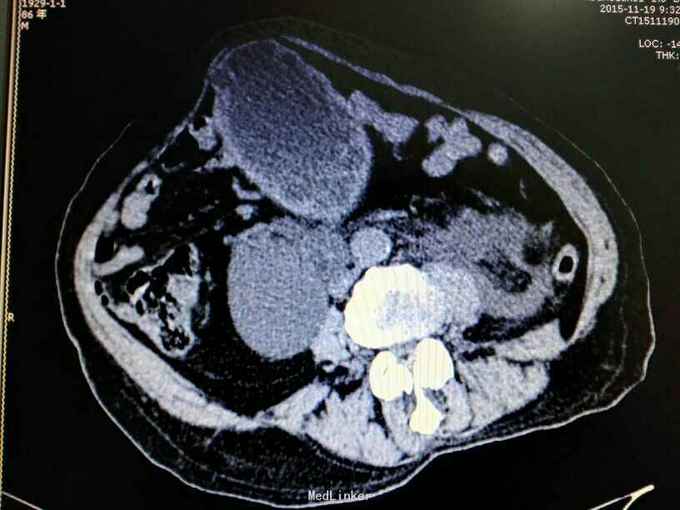

男性,87岁,进行性排尿困难10年,小便不能自解2天入院。无血尿,无发热、腰痛。一直口服藏药治疗前列腺增生症。既往无高血压、糖尿病。

腹部明显膨隆。耻骨上膀胱区扣浊。肾区无扣痛。尿常规少许白细胞。肌酐506,电解质正常。Hb116。

前列腺增生症 尿潴留 双肾积水 肾功能不全,膀胱结石,尿路感染,双肾多发囊肿。给予留置导尿,间断分次放尿后,出现肉眼血尿,持续膀胱冲洗,颜色较红,伴血凝块间断堵管。